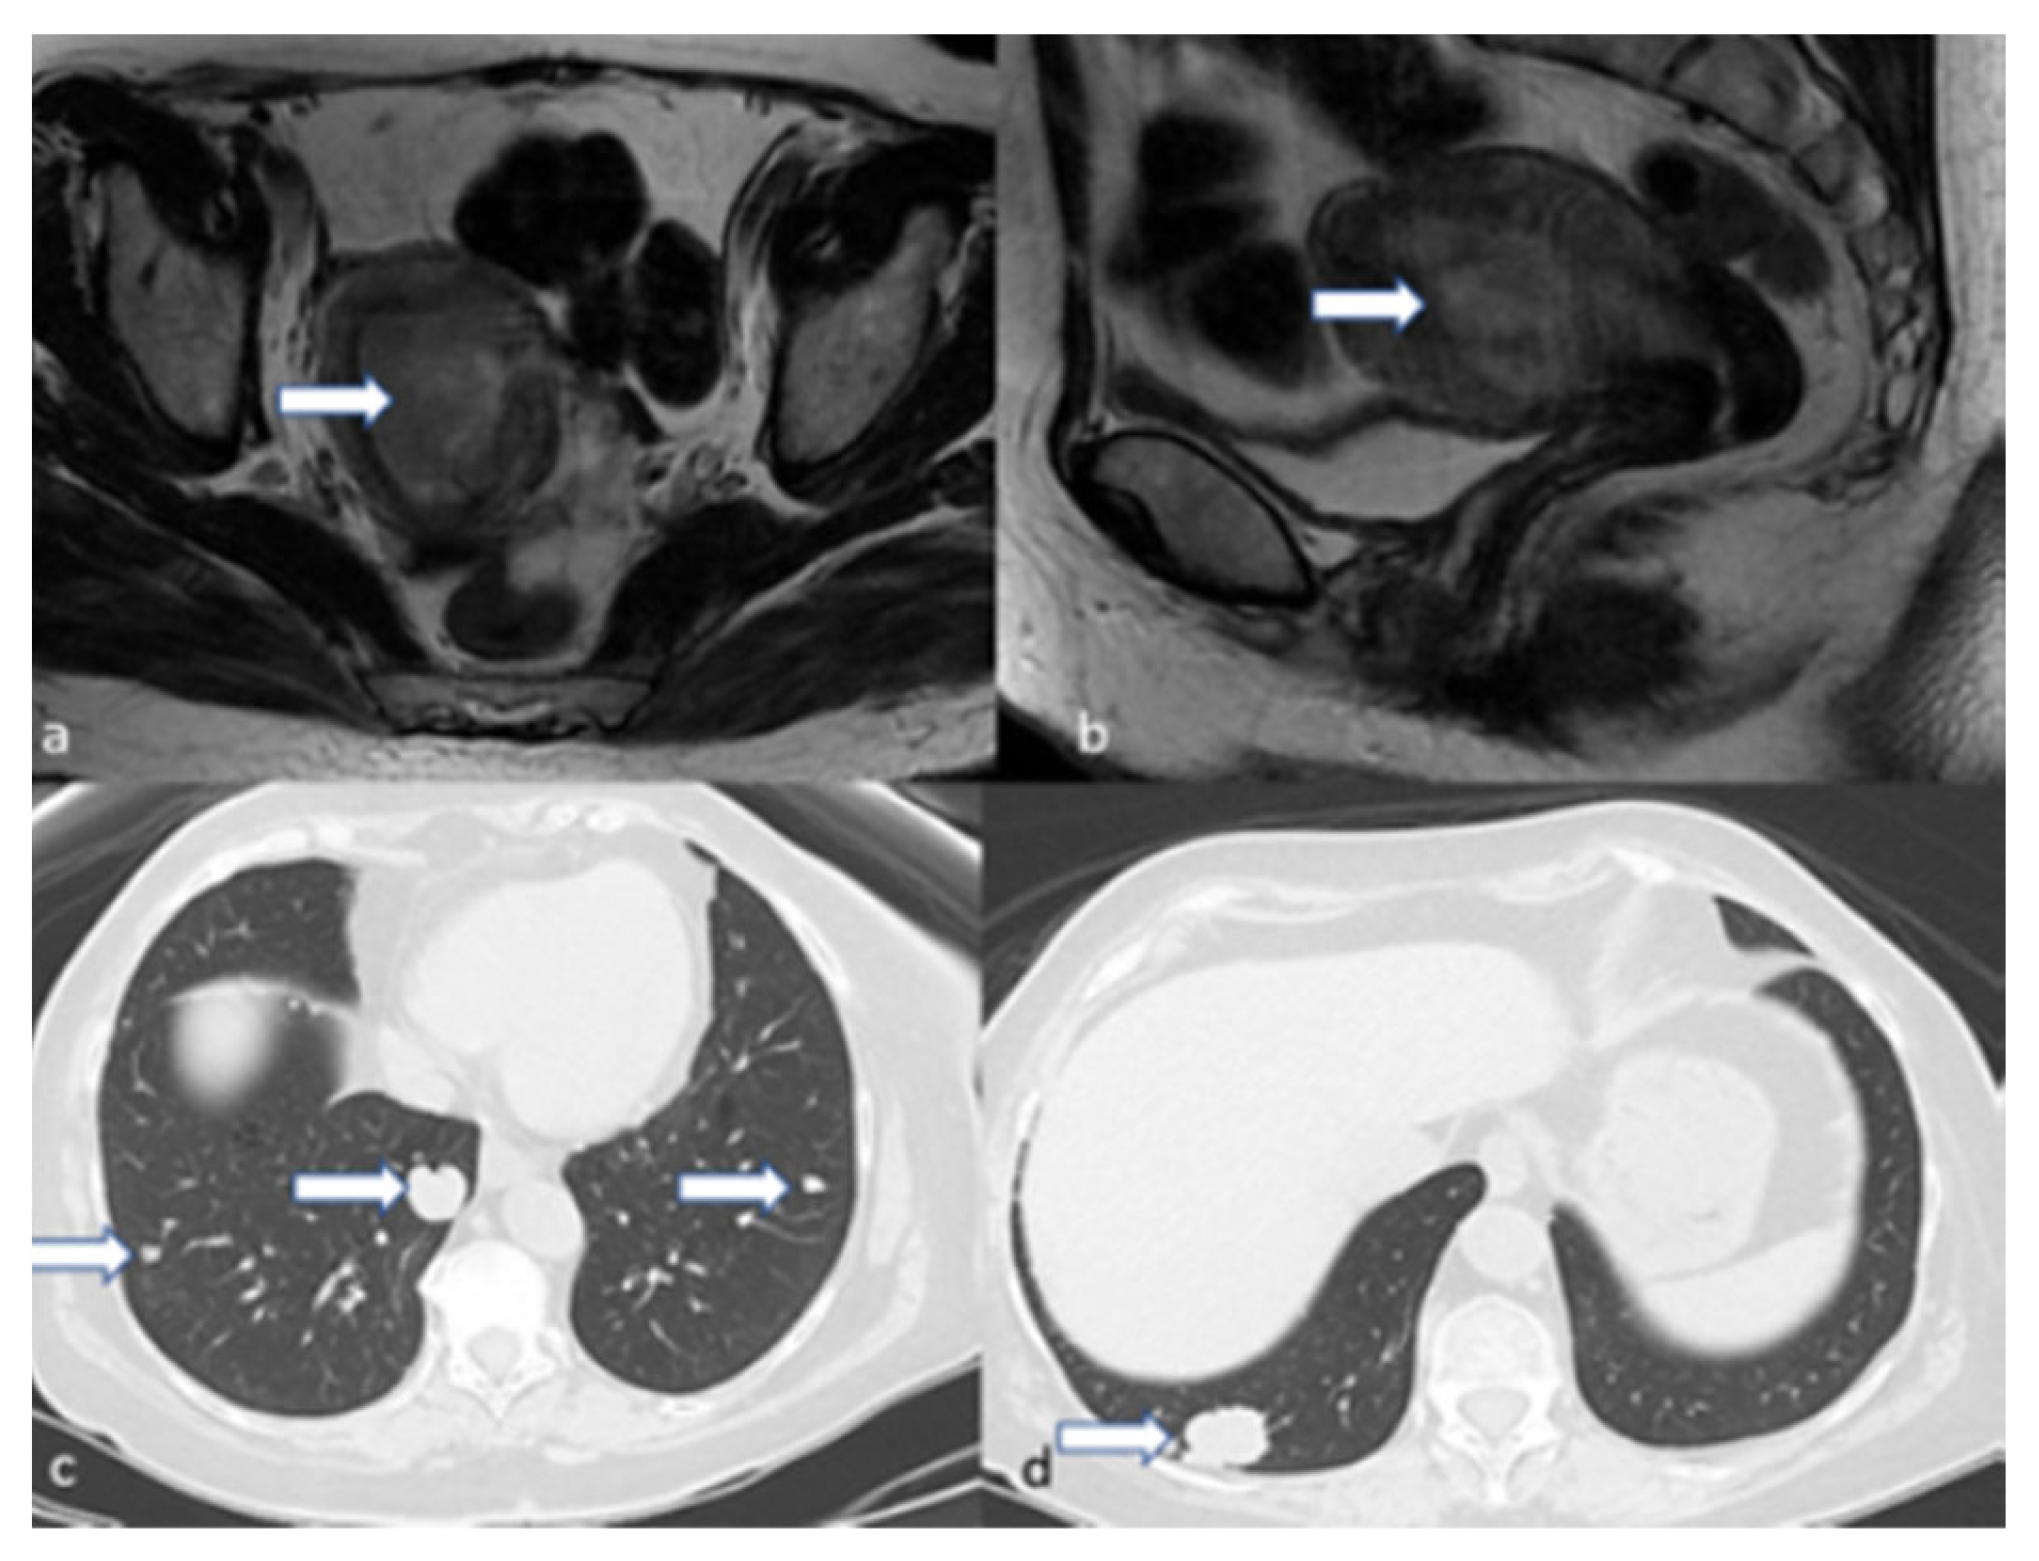

4.4. Stage IV

5.3. Magnetic Resonance Imaging (MRI)

- Maheshwari, E.; Nougaret, S.; Stein, E.B.; Rauch, G.M.; Hwang, K.-P.; Stafford, R.J.; Klopp, A.H.; Soliman, P.T.; Maturen, K.E.; Rockall, A.G.; et al. Update on MRI in Evaluation and Treatment of Endometrial Cancer. RadioGraphics 2022, 42, 2112–2130. [Google Scholar] [CrossRef] [PubMed]

- Saleh, M.; Virarkar, M.; Bhosale, P.; El Sherif, S.; Javadi, S.; Faria, S.C. Endometrial Cancer, the Current International Federation of Gynecology and Obstetrics Staging System, and the Role of Imaging. J. Comput. Assist. Tomogr. 2020, 44, 714–729. [Google Scholar] [CrossRef]

- Fasmer, K.E.; Gulati, A.; Dybvik, J.A.; Wagner-Larsen, K.S.; Lura, N.; Salvesen, Ø.; Forsse, D.; Trovik, J.; Pijnenborg, J.M.A.; Krakstad, C.; et al. Preoperative pelvic MRI and 2-[(18)F]FDG PET/CT for lymph node staging and prognostication in endometrial cancer-time to revisit current imaging guidelines? Eur. Radiol. 2023, 33, 221–232. [Google Scholar] [CrossRef]

- Stewart, K.I.; Chasen, B.; Erwin, W.; Fleming, N.; Westin, S.N.; Dioun, S.; Frumovitz, M.; Ramirez, P.T.; Lu, K.H.; Wong, F.; et al. Preoperative PET/CT does not accurately detect extrauterine disease in patients with newly diagnosed high-risk endometrial cancer: A prospective study. Cancer 2019, 125, 3347–3353. [Google Scholar] [CrossRef] [PubMed]